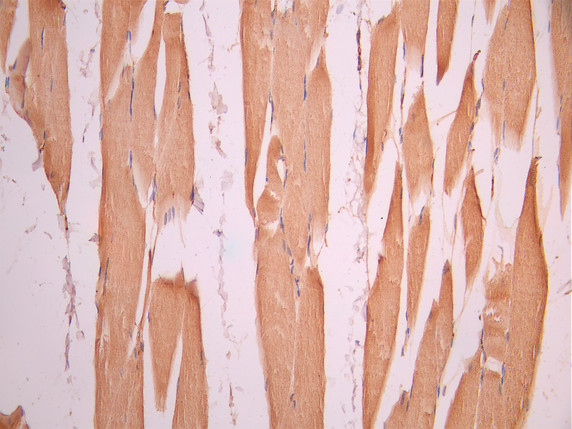

IHC image of CSB-RA900765A0HU diluted at 1:100 and staining in paraffin-embedded human skeletal muscle tissue performed on a Leica BondTM system. After dewaxing and hydration, antigen retrieval was mediated by high pressure in a citrate buffer (pH 6.0). Section was blocked with 10% normal goat serum 30min at RT. Then primary antibody (1% BSA) was incubated at 4°C overnight. The primary is detected by a Goat anti-rabbit polymer IgG labeled by HRP and visualized using 0.05% DAB.